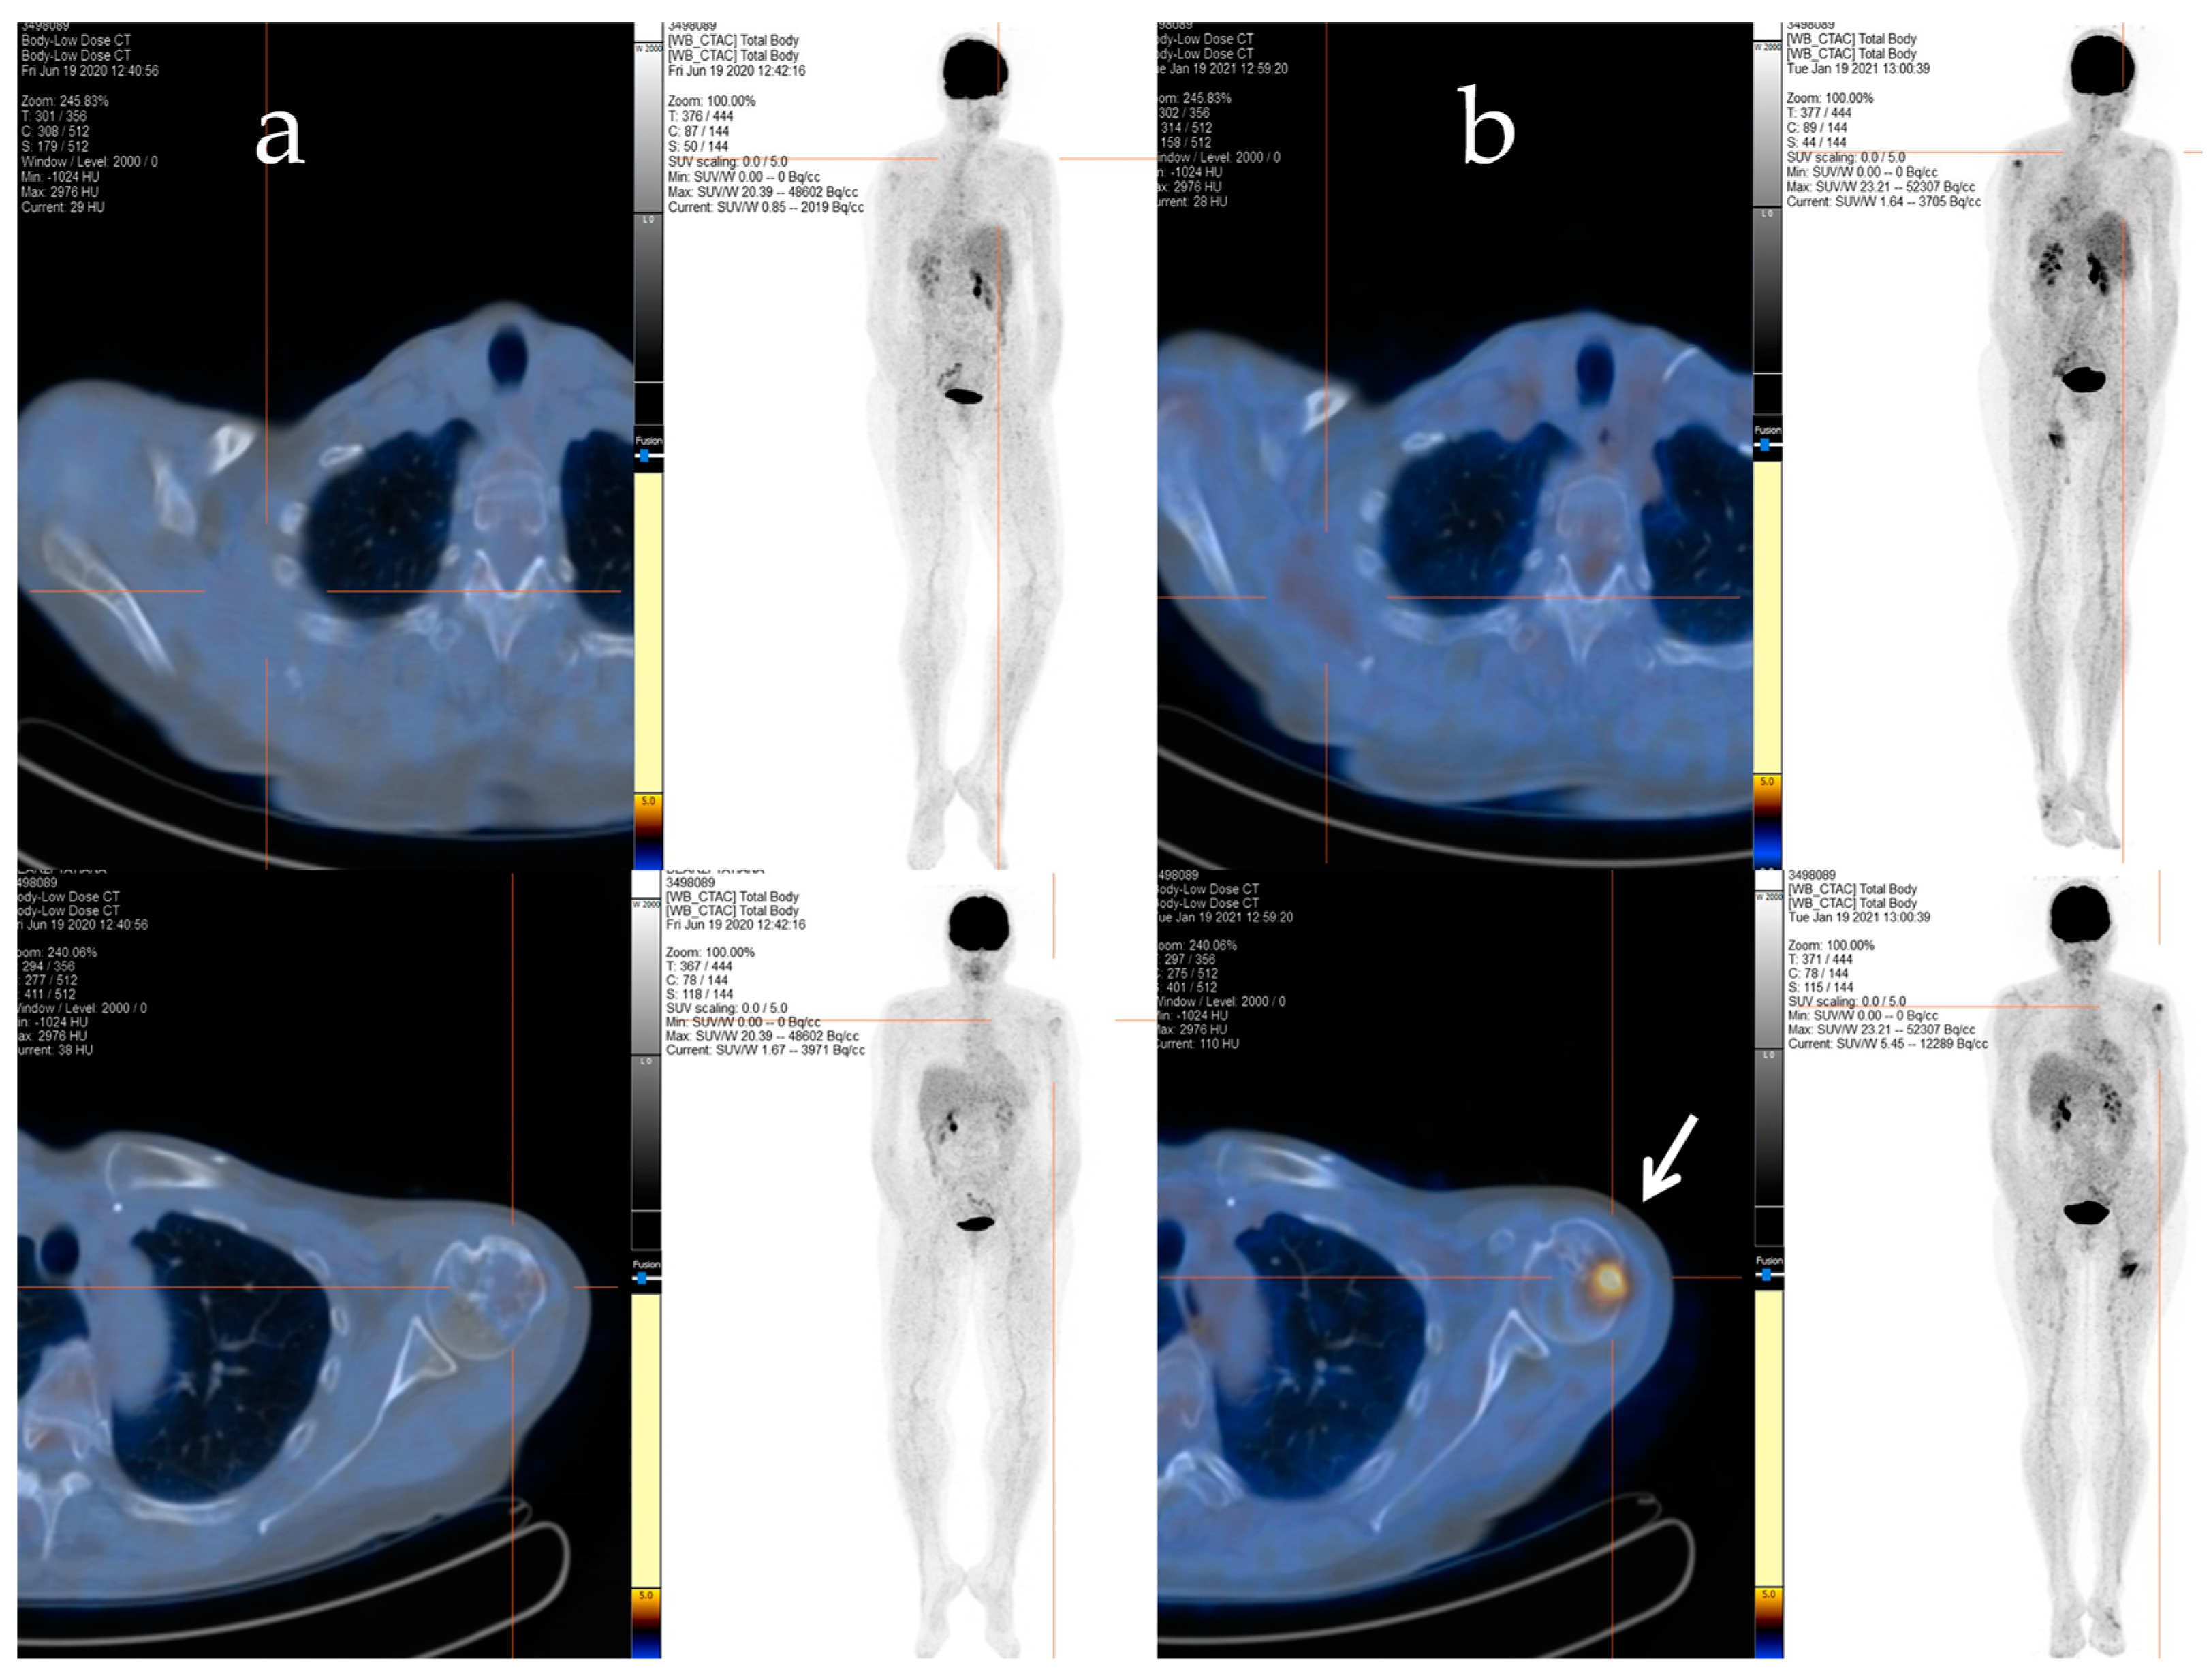

2.2. Clinical Journey of Index Case